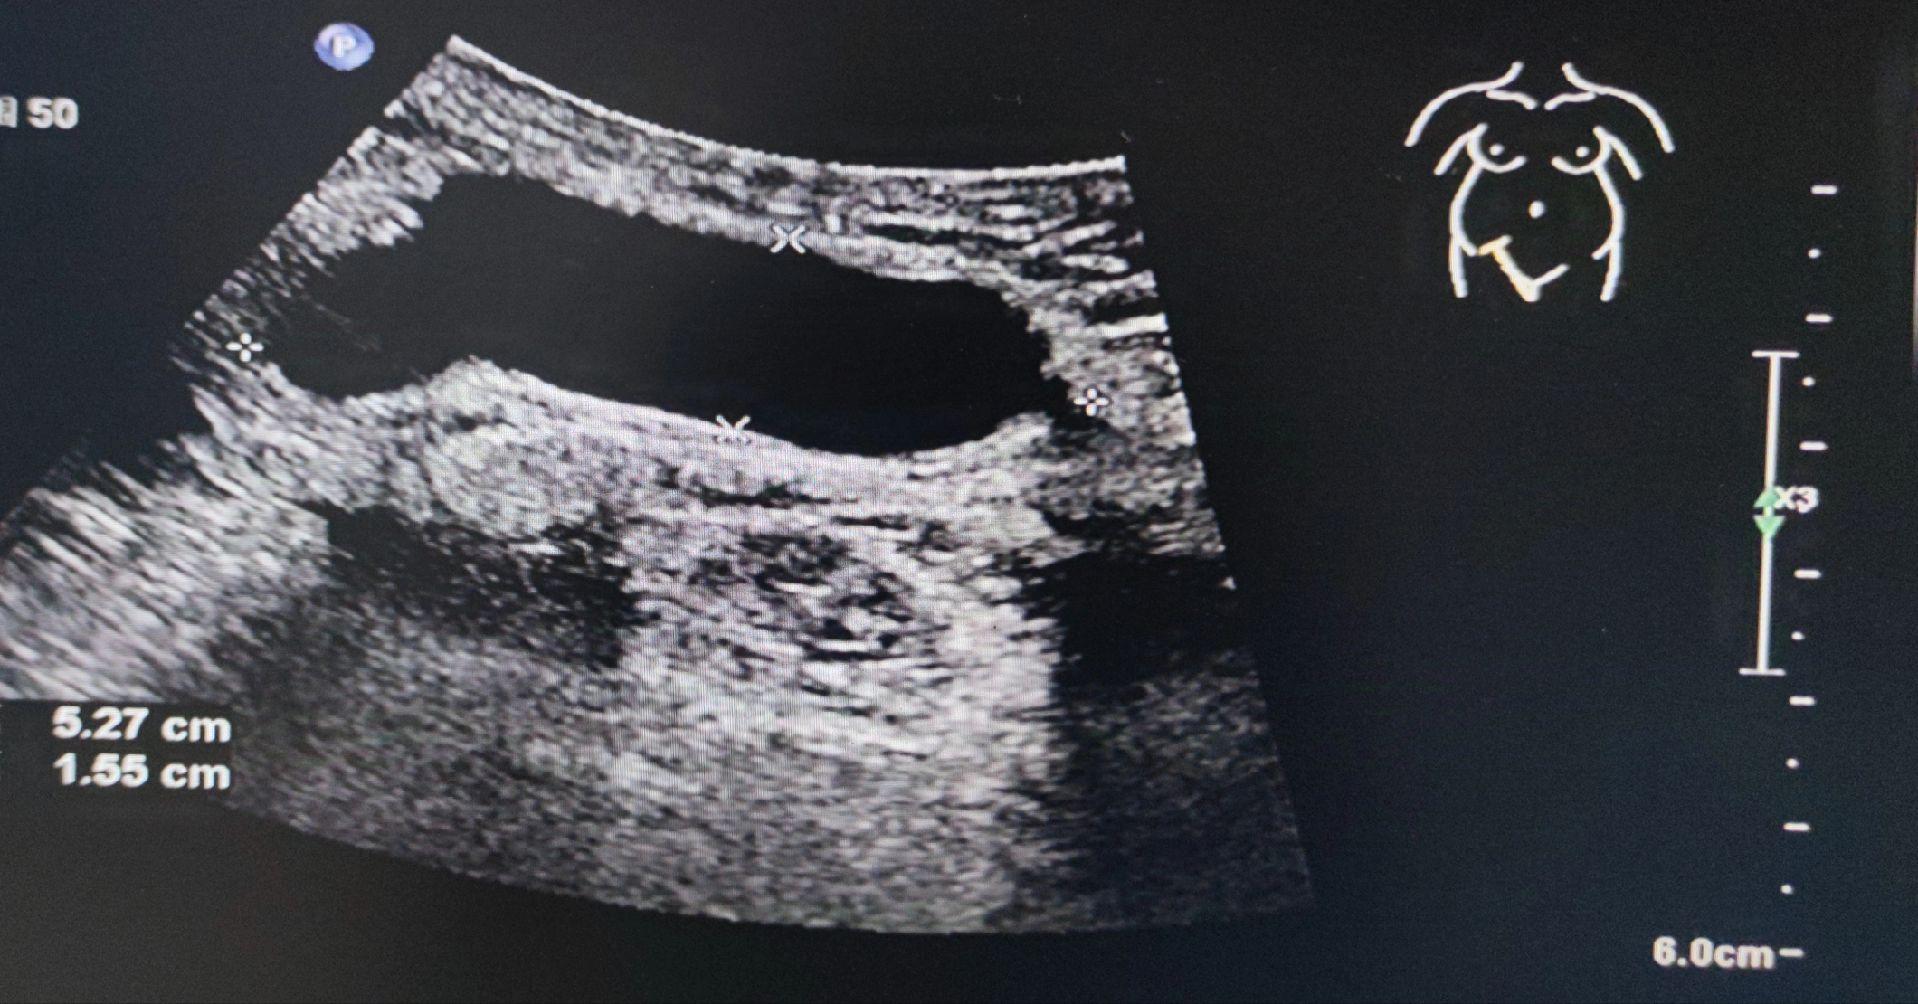

子宫圆韧带囊肿。女,41岁,腹股沟去包块来检查 子宫圆韧带囊肿又叫Nuck囊肿,少见。囊肿大小及形态不随体位改变而变化,有别于腹股沟斜疝